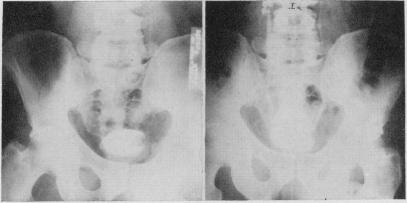

Sigmoid segment substitutes for bladder.